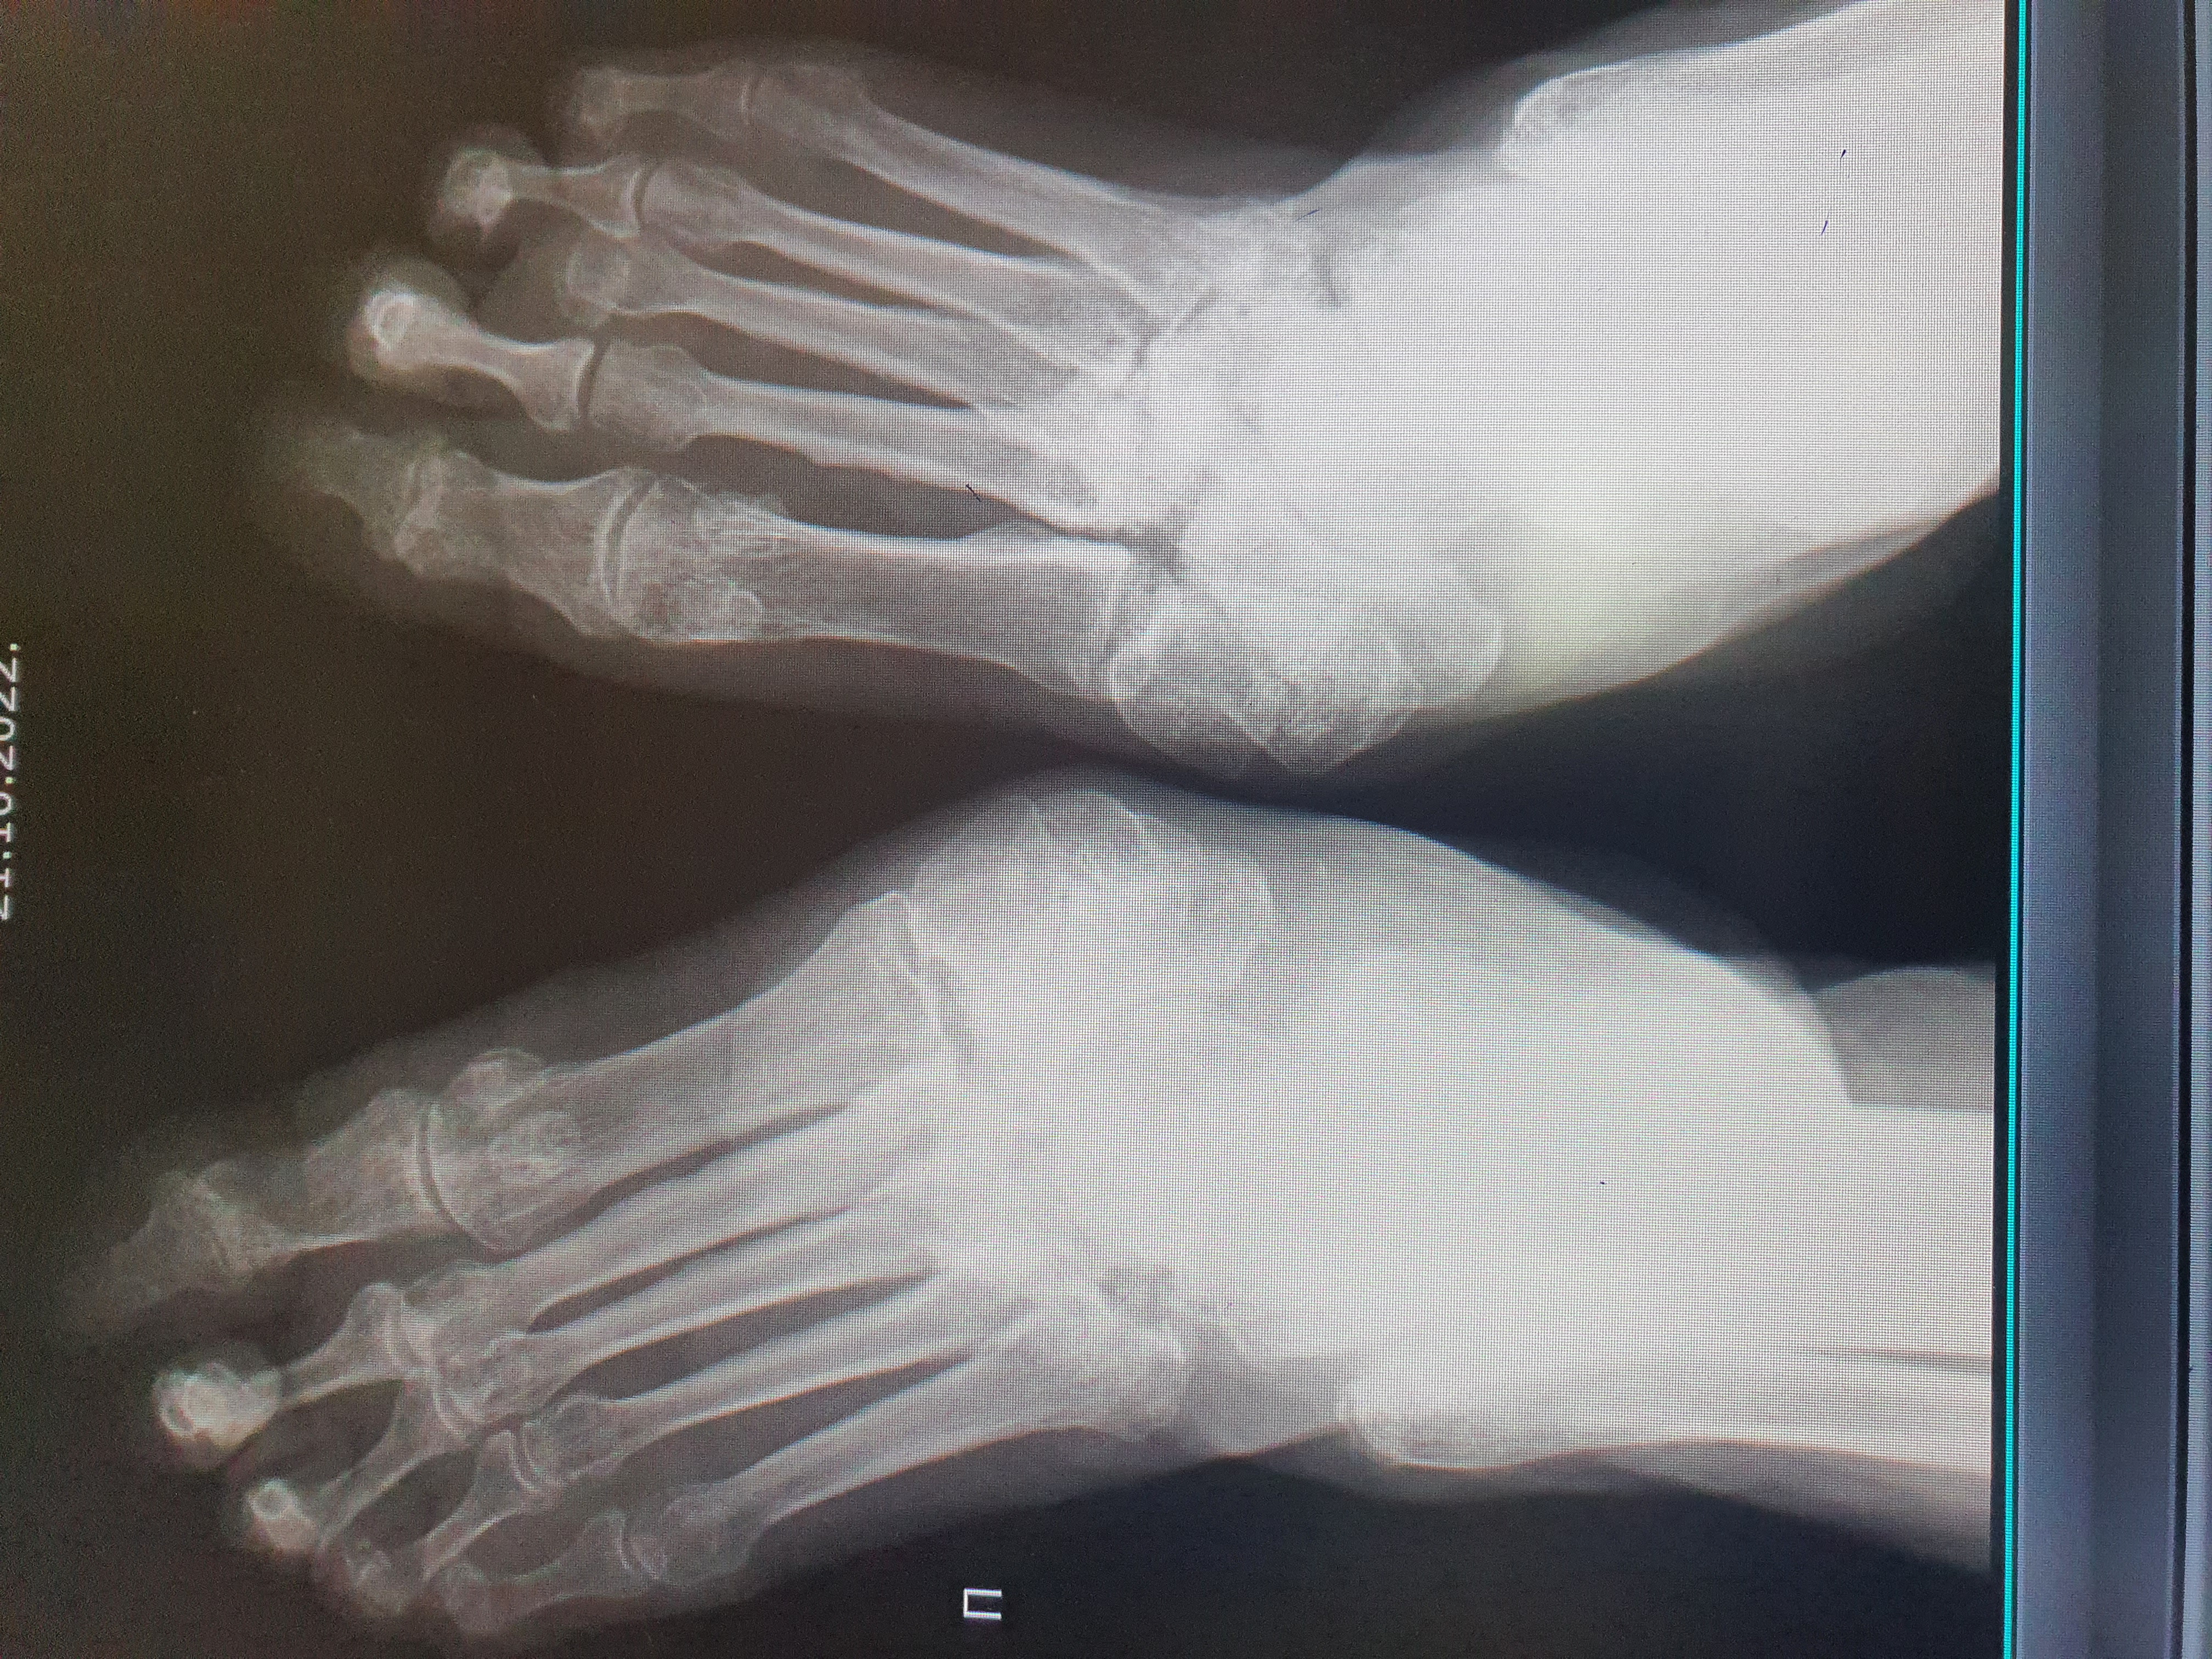

Здравствуйте, пациентка в течении длительного времени болеет диабетом. Выставляют болезнь Шарко. Впервые вижу такое заболевание и рентгенологическую картину. Уважаемые коллеги, подскажите, как бы вы описали данный снимок. Mon, 24/10/2022 - 08:07 #1 Андрей Юрьевич Offline Last seen: 2 weeks 3 days ago Joined: 16.11.2008 - 22:16 Posts: 18106 Есть такая кнопка "Вставить" Андрей Юрьевич Tue, 25/10/2022 - 04:30 #2 Андреева Offline Last seen: 3 years 6 months ago Joined: 02.06.2020 - 06:26 Posts: 12 Спасибо